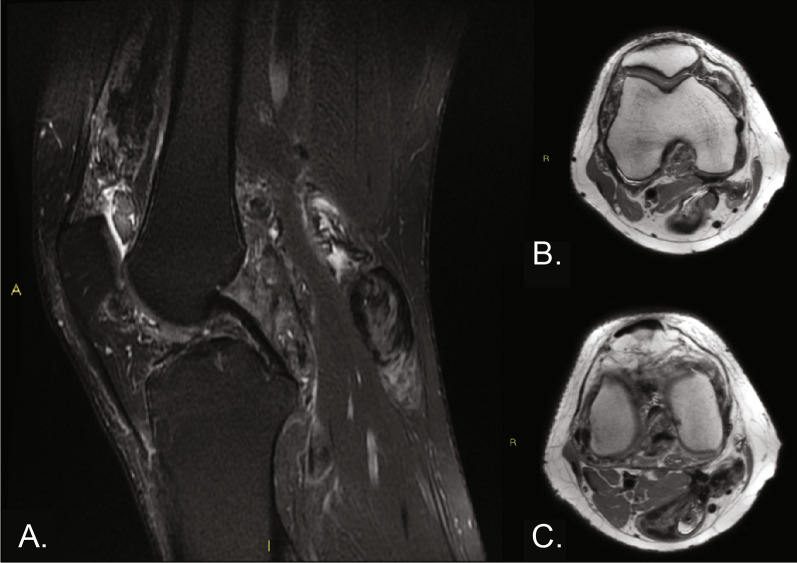

Case description: A 32-year-old man presented with intra-articular diffuse TGCT with pain and received noncurative treatment for 5 years (2014-2019). In 2019, the patient was found to have extensive disease accompanied by pain and limited range of motion. The patient's case was presented to a sarcoma multidisciplinary tumor board, who determined that surgery would cause significant morbidity and macroscopic residual tumor. As a result of the extent of disease, young age, and otherwise good health, treatment with pexidartinib was started through a compassionate use program at 800 mg/day. After dose reductions to pexidartinib at 400 mg/day and then 200 mg/day as a result of creatine phosphokinase elevations, the patient achieved a complete response after 2 years of treatment; pain was reduced and mobility was restored. The patient reported no side effects related to pexidartinib treatment. Treatment was stopped in 2022 for future family planning. After pexidartinib therapy was interrupted, the patient's wife had a successful pregnancy and delivery; however, the disease showed a slow but constant clinical deterioration, with a reduction in the range of movement of the affected knee and an apparent increase in widespread TGCT nodules.

Abstract Image